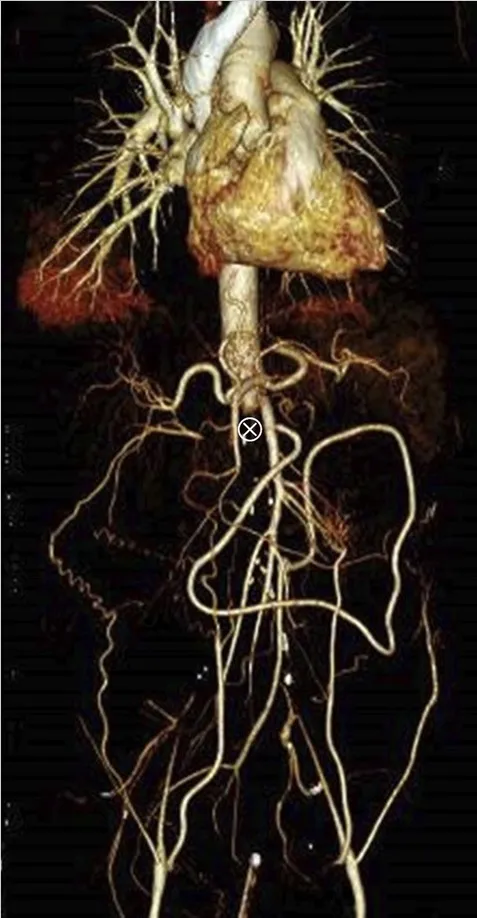

Realizado USG renal com Doppler que mostrou ecogenicidade e tamanho renal normais, mas sinais de oclusão aórtica na emergência da artéria mesentérica superior, o que foi confirmado por tomografia computadorizada com contraste (Figura 1).

A TC também revelou importante circulação colateral na parede abdominal, permitindo suprimento sanguíneo suficiente para os membros inferiores. Apenas o rim esquerdo mostrou captação residual de contraste (Figura 1), sugerindo rim direito isquêmico.

TC com contraste (reconstrução 3D) mostrando oclusão aguda da aorta justa-superior da artéria mesentérica. (A) Oclusão aórtica justa-superior à artéria mesentérica (marcada com um ⊗) juntamente com vasos colaterais na parede abdominal (B) Rim esquerdo com realce de contraste e rim direito sem realce sugerindo falta de perfusão renal.